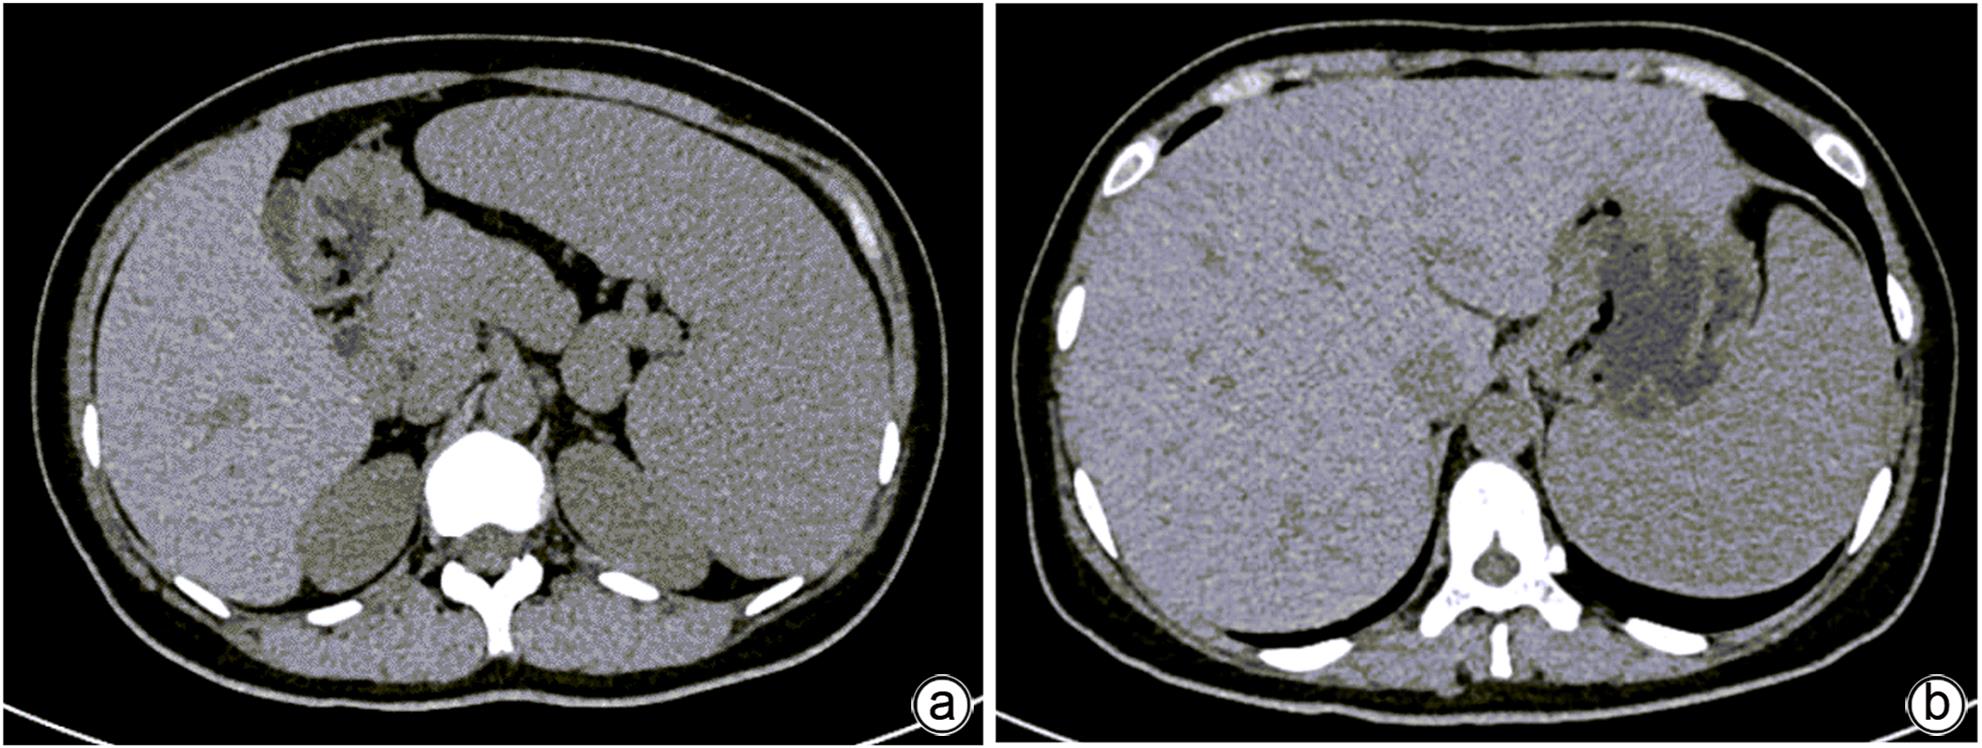

New Technology and Therapeutic Strategy

Efficacy of endoscopic retrograde cholangiopancreatography combined with electrohydraulic lithotripsy under the direct view of eyeMax biliary-pancreatic imaging system in treatment of difficult choledocholithiasis

Liying TAO, Hongguang WANG, Qingmei GUO, Lianyu PIAO, Xiang GUO, Libin RUAN, Shizhu LIU, Zhen SUN

2024, 40(2): 351-355. DOI: 10.12449/JCH240220

Abstract(1229) HTML (316) PDF (807KB)(110)

Abstract:

Objective  To investigate the safety and efficacy of endoscopic retrograde cholangiopancreatography (ERCP) combined with electrohydraulic lithotripsy under the direct view of eyeMax biliary-pancreatic imaging system in the treatment of difficult choledocholithiasis.  Methods  A retrospective analysis was performed for the clinical data of 12 patients with difficult choledocholithiasis who underwent ERCP and electrohydraulic lithotripsy under the direct view of eyeMax biliary-pancreatic imaging system in Department of Gastroenterology, Jilin People’s Hospital, from May to November 2022. The clinical effect of lithotripsy and lithotomy was observed, and postoperative complications and time of surgical operation were assessed.  Results  Among the 12 patients, 11 (91.67%) were successfully treated by electrohydraulic lithotripsy under direct view, 9 (75.00%) achieved first-attempt success in lithotripsy, and 11 (91.67%) had complete removal of calculi; 1 patient was found to have stenosis of the bile ducts caused by multiple biliary tract surgeries, and grade Ⅱ intrahepatic bile duct stones above the sites of stenosis were removed under direct view, but there were still residues of grade Ⅲ intrahepatic bile duct stones, which led to the fact that complete calculus removal was not achieved. The mean time of ERCP operation was 91.3±26.2 minutes, including a time of 41.8±22.2 minutes for energy lithotripsy. There were 2 cases of postoperative biliary tract infection which were improved after anti-infective therapy, 2 cases of hyperamylasemia which were not given special treatment, and 3 cases of mild pancreatitis which were improved after symptomatic medication, and there were no complications such as bleeding and perforation.  Conclusion  ERCP combined with electrohydraulic lithotripsy under the direct view of eyeMax biliary-pancreatic imaging system is safe, effective, and feasible in the treatment of difficult choledocholithiasis.